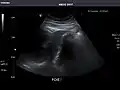

Right kidney -